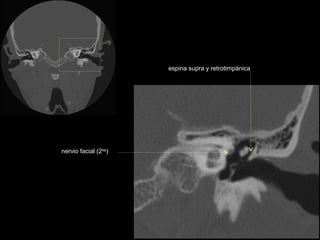

CATEDRA DE RADIOLOGIA U.N.L.P.   Hueso temporal normal              Edición 2002

seno maxilar

conducto

carotídeo

auditivo externo

protuberancia

occipital externa

trompa de Eustaquio

conducto auditivo externo

celdillas mastoideas

eminencia piramidal

seno timpánico

receso del n. facial

nervio facial (3era)

estribo (cruras)

nervio facial

ventana oval

martillo

yunque

cóclea

vestíbulo

conducto semicircular externo

articulación yunque/martillo

conducto auditivo interno

conducto semicircular posterior

antro mastoideo

celdillas retrolaberínticas

conducto semicircular

superior

conducto semicircular superior

cabeza del martillo

procidencia de meninges

tendón tensor del tímpano

conducto carotídeo

espina supra y retrotimpánica

nervio facial (2da)

nervio facial (1era)

cresta falciforme

promontorio

estribo

membrana

timpánica

externo

ventana redonda